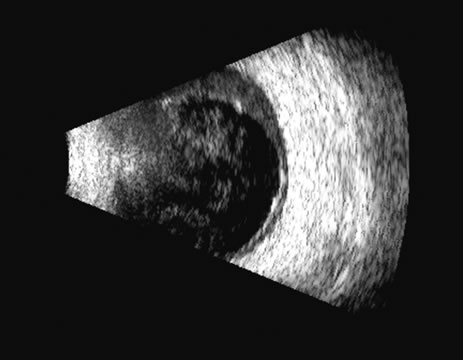

The choroid, like the retina, is highly reflective and may resemble the retina when detached. Its thickness, which includes the retina, Bruch's membrane, and the choriocapillaris (tunica ruyschiana) is not usually differentiable when measured with routine ultrasound;12 however, it may be measured with digital techniques.18 Anatomically, the choroidal elevation is usually a smoothly round, convex surface, limited posteriorly by the vortex veins and anteriorly at any point up to the base of the iris (Fig. 17). The choroidal space should be examined for echoes (blood) or a clear zone, as seen with effusion or the serous part of a hemorrhage. In evaluating membranes from retina or choroid, it is always helpful to repeat the examinations at a later time.

Fig. 17. This patient with a Molteno tube was treated for glaucoma. The top 50 MHz B-scan clearly shows the Molteno Tube (arrow). The bottom 10 MHz B-scan of the same patient demonstrates a choroidal detachment (large arrow) with associated posterior retinal detachment (small arrow). Choroidal elevations are typically convex, highly reflective surfaces with posterior limitation at the vortex vessels. Retina will always attach at the optic nerve. Choroidal elevations are often noted in several quadrants, as seen here.